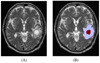

We propose a new model to simulate the three-dimensional (3-D) growth of glioblastomas multiforma (GBMs), the most aggressive glial tumors. The GBM speed of growth depends on the invaded tissue: faster in white than in gray matter, it is stopped by the dura or the ventricles. These different structures are introduced into the model using an atlas matching technique. The atlas includes both the segmentations of anatomical structures and diffusion information in white matter fibers. We use the finite element method (FEM) to simulate the invasion of the GBM in the brain parenchyma and its mechanical interaction with the invaded structures (mass effect). Depending on the considered tissue, the former effect is modeled with a reaction-diffusion or a Gompertz equation, while the latter is based on a linear elastic brain constitutive equation. In addition, we propose a new coupling equation taking into account the mechanical influence of the tumor cells on the invaded tissues. The tumor growth simulation is assessed by comparing the in-silico GBM growth with the real growth observed on two magnetic resonance images (MRIs) of a patient acquired with 6 mo difference. Results show the feasibility of this new conceptual approach and justifies its further evaluation.